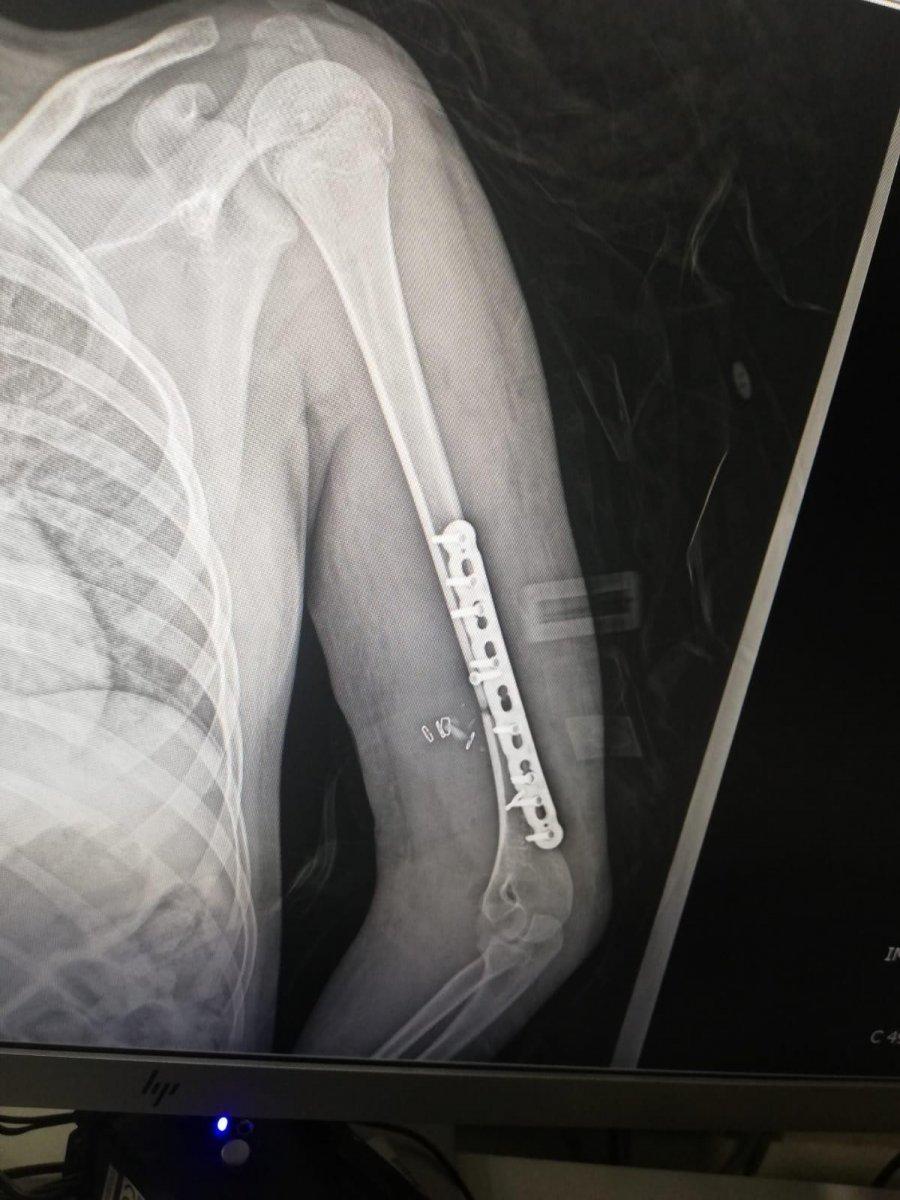

Burada ilk tedavisi yapılan küçük kızın sol bacak ve kolu ile kalça ve kuyruk kemiğinin kırıldığı tespit edilmiş ve Bezmialem Vakıf Üniversitesi Hastanesi'ne kaldırılarak tedavi altına alınmıştı. 9 ay geçen olayın sonrasında Elif Koşucu’nun düşmeye bağlı olarak topallayarak yürüyebildiği, sol koluna platin takıldığı ve sol ayak bilekliğine de yürüyebilmesi için özel bir apart takıldığı öğrenildi.